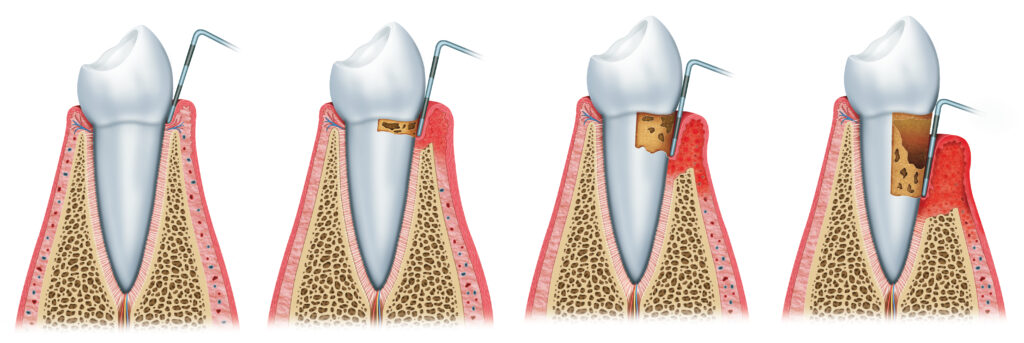

Periodontologia zajmuje się leczeniem chorób przyzębia potocznie zwanymi parodontozą.

Stan zapalny przyzębia czyli tkanek utrzymujących ząb w kości oraz kości otaczającej ząb. Powodują go agresywne bakterie kumulujące się w kamieniu nazębnym nad i poddziąsłowym. Kamień nazębny to zmineralizowana płytka nazębna, która zalega na zębach w wyniku niewłaściwej higieny jamy ustnej.

Dotykanie sondą periodontologiczną okolicy przyzębia pozwala ocenić:

- krawawienie dziąseł

- obecność płytki nazębnej

- obecność kamienia nazębnego

- obecność kieszonek przyzębnych oraz ich głębokość

- kieszonki dziąsłowe > 3,5 mm świadczą o chorobie przyzębia